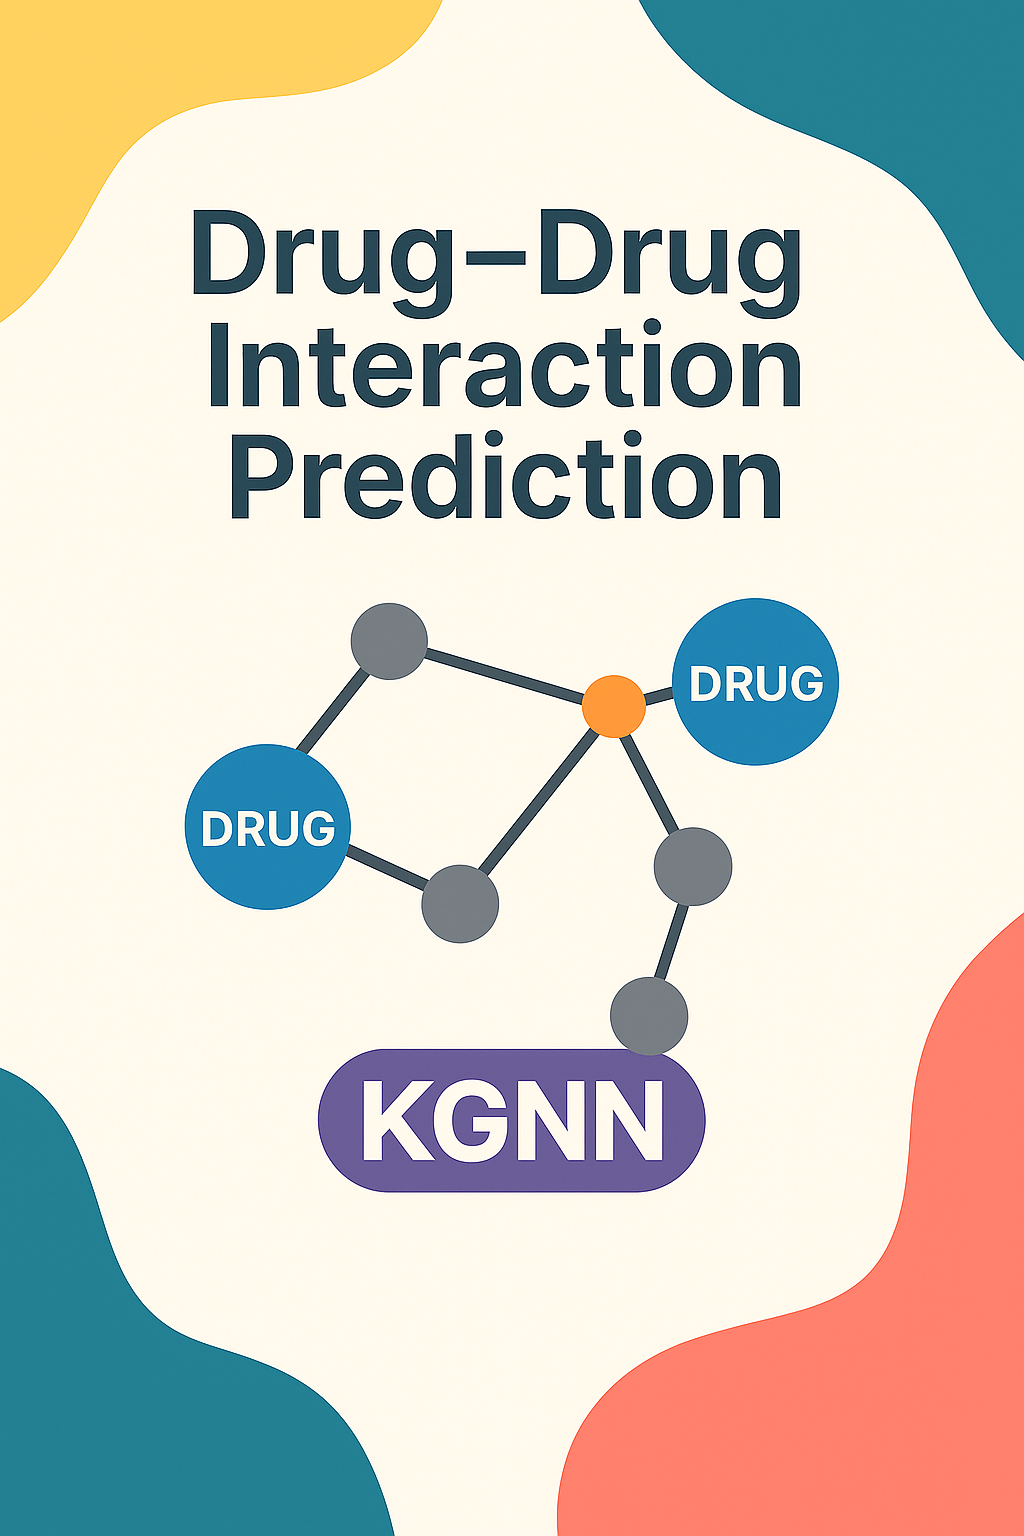

Knowledge Graph DDI Prediction

Web application for predicting drug-drug interactions DDIs using KGNNs.

Learn More →